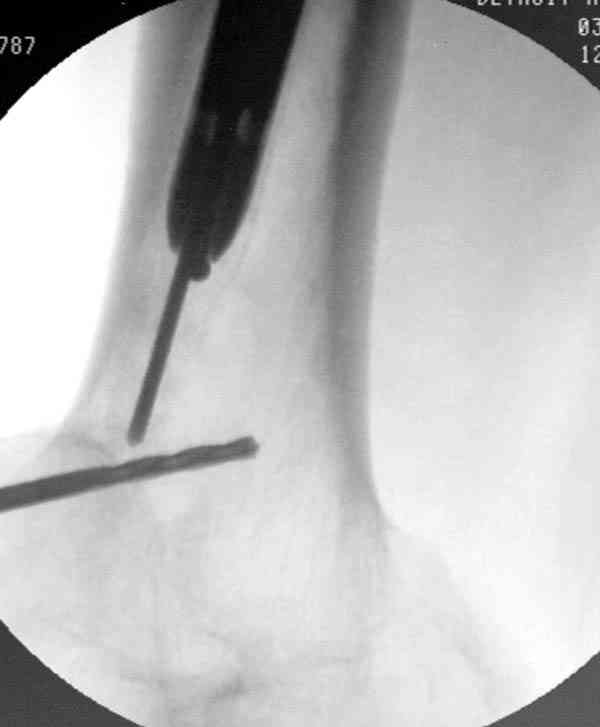

Приспособление для удаления сломанных штифтов и наличие ЭОП облегчит

задачу. При отсутствии крючка тогда можно применить обычный длинный

ball pointed guide wire от интрамедулярного набора. Проволока,

пропущенная за пределы гвоздя и зажатая другая вытащат сломанный

конец штифта без проблем.